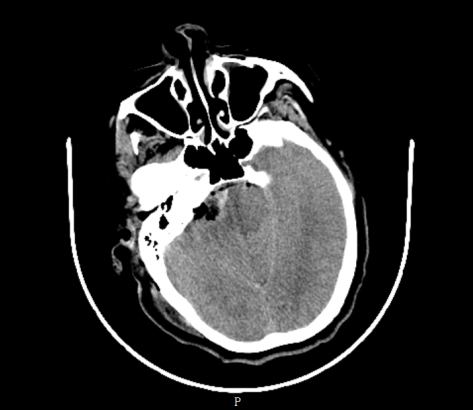

术后CT

术前精心准备后,4月7日,肖炳祥和神经外科业务主任张卫华及王磊波,共同为患者完成手术。

术后,患者神志清楚,右侧听力保留,无明显面瘫表现,第9天顺利出院。